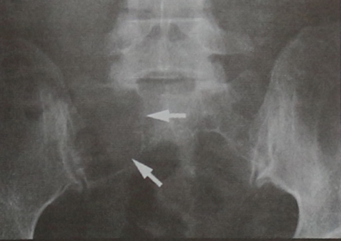

Диагностика

Наиболее прогрессивными методами диагностики рака позвоночника являются КТ (компьютерная томография) и МРТ (магнитно-резонансная томография). С их помощью можно определить точное расположение опухоли, ее форму, размер ее отношение к соседним органам и тканям и наличие метастазов.

КТ позвоночника проводится с помощью новейшего оборудования - компьютерного томографа. Это аппарат, состоящий из кольца, оснащенного детекторами, и двигающейся кушетки, на которой лежит пациент. Кушетка входит в кольцо, что позволяет специальной установке выполнять снимки позвоночника больного в разных проекциях и под разными углами.